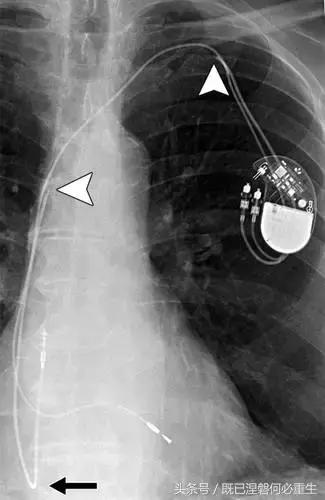

图 1A B 在75岁男性中植入式心律转复除颤器(ICD)的正常部件。

A,额叶胸片显示Medtronic(公司名字)单室ICD。 ICD的基本组件包括发生器,导线和围绕右心室(RV)导线的冲击线圈。 该系统还具有上腔静脉(SVC)中的冲击线圈,其可能不存在于所有系统中。 起搏器没有冲击线圈。 铅固定(见图8A)固定到胸部,并且可能或可能不在胸部X光片上可见。

B,引线通过头连接到发电机(黄色),其保持一个或多个连接端口。 所示系统需要三个端口(一个用于双极起搏或感测元件,一个用于RV休克线圈,一个用于SVC冲击线圈)。 正确放置的引脚将延伸超出连接器(见图9)。 制造商的标志和单个设备标识符的字体被反转,因为发电机被定向以允许在发生器口袋中适当的引线盘绕。 这种定位被设计成减少扭结的风险,这可能导致断裂。 有关制造商徽标的更多信息,请参见图4。